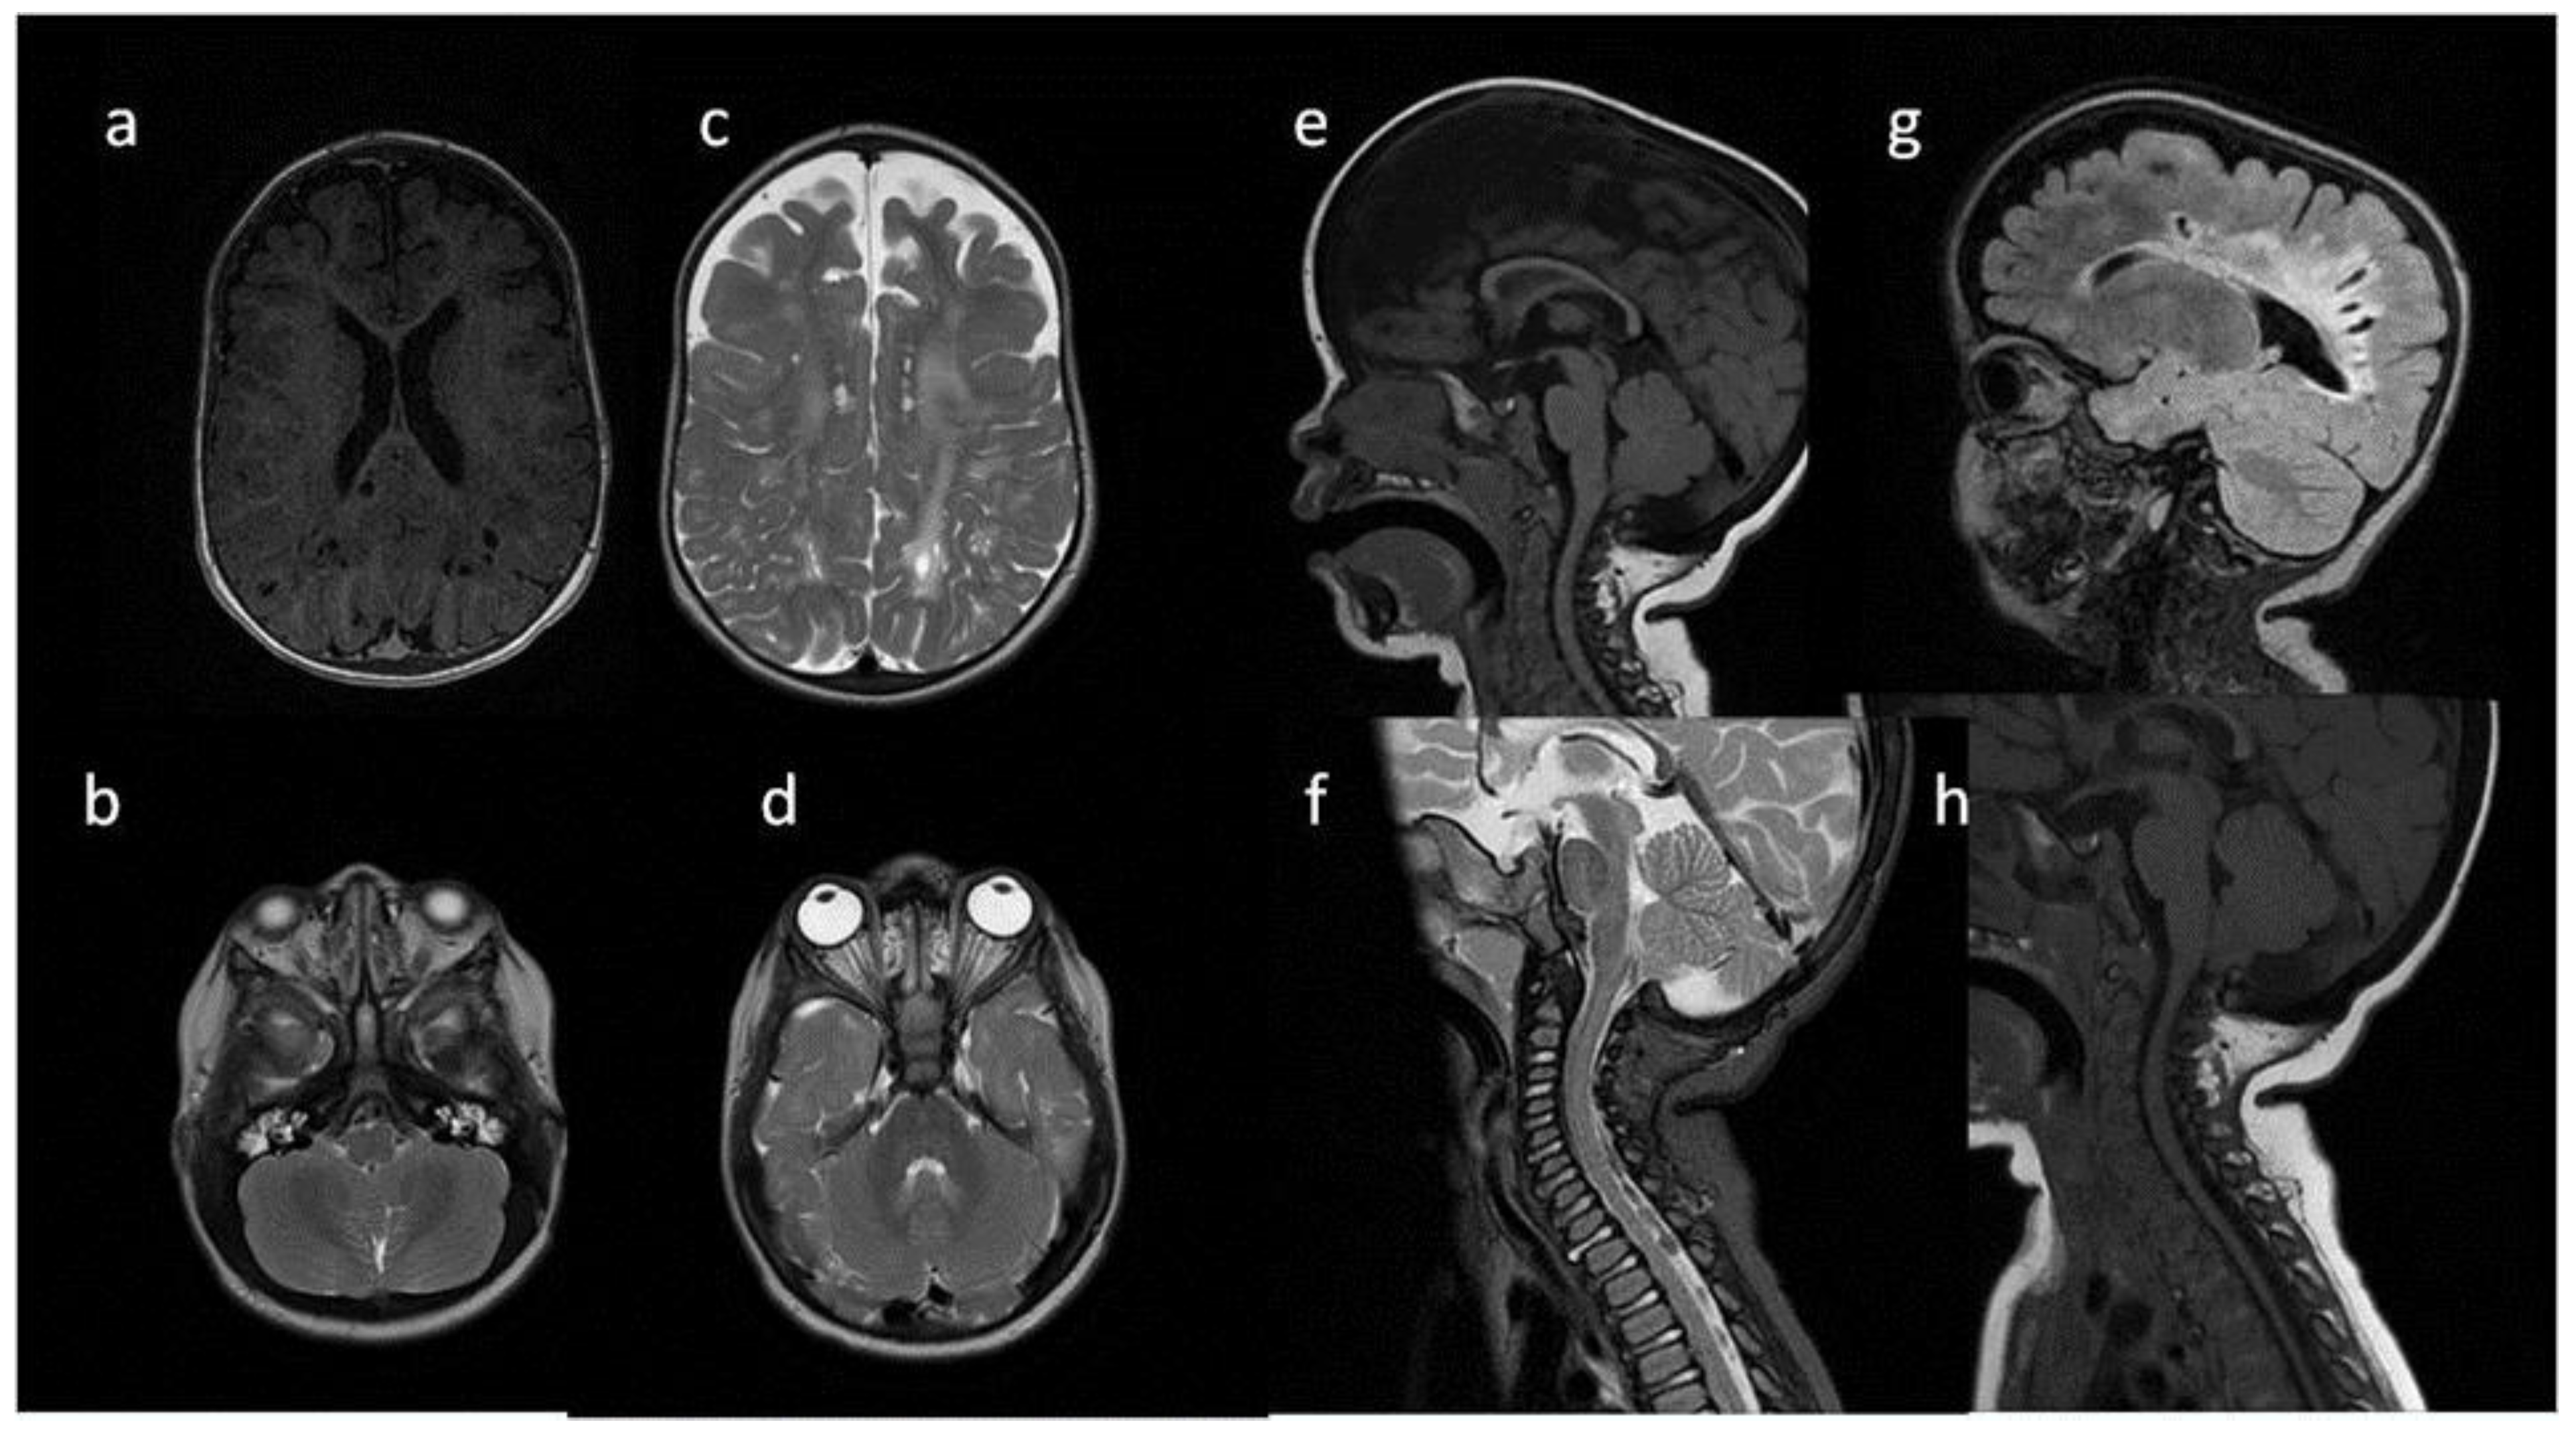

| Patient No | 1 | 2 | 3 | 4 | 5 | |

|---|---|---|---|---|---|---|

| age at exam | 4 mo | 3 yo | 1 y 2 mo | 1 y 11 mo | 3 y 2 mo | 14 yo |

| radiological imaging | ||||||

| WM signal abnormalities | + | + | + | |||

| areas of delayed myelination | + | + | + | + | + | |

| enlarged perivascular spaces | + | + | + | + | ||

| narrow corpus callosum | + | +/− | + | + | ||

| prominent ventricular system | +/− | + | +/− | + | + | |

| arachnoid cyst | + | + | ||||

| optic nerve sheath enlargement | + | + | ||||

| J-shaped sella turcica | + | + | + | +/− | + | +/− |

| craniocervical junction distortion | + | +/− | + | + | ||

| posterior fossa horns | + | + | + | + | ||

| fluid effusion temporal bone | + | + | + | + | +/− | |

| closed sagittal suture | + | + | + | |||

| vertebral bodies deformity | + | + | ||||

| intervertebral disc anomalies | + | + | ||||